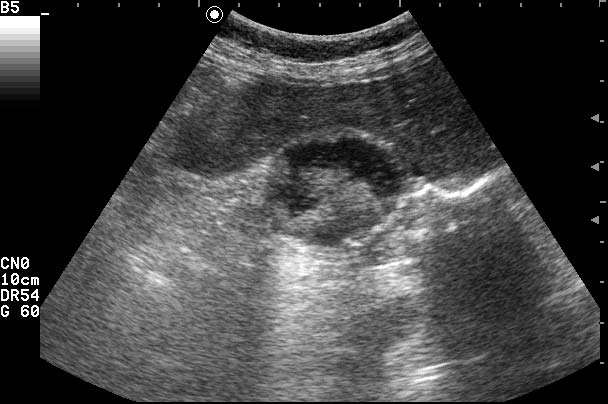

ЖКБ. Эмпиема желчного пузыря.

Женщина 70 лет с болями в правом подреберье и интоксикацией.

Острый калькулезный холецистит,осложненный эмпиемой. Второй вариант-"замазкообразная"желчь в просвете воспаленного пузыря.

Первый вариант мне нравится больше.

Второй маловероятен в связи с описанной клиникой.

О.обструктивный калькулезный холецистит. Эмпиема желчного пузыря.

Но,и первый вариант возможен,стенка дна ж.пузыря НЕЦЕЛАЯ,возможна перфорация.